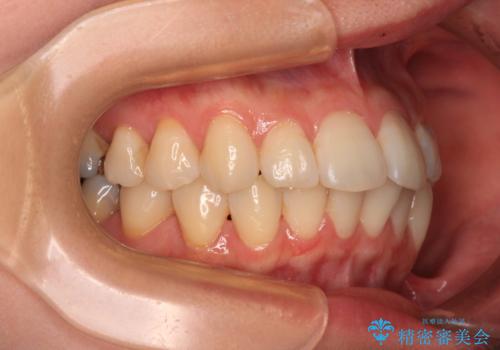

- 前歯のデコボコや、やや突出した感じを気にして来院された患者様です。

抜歯矯正を必要とするほど口元の突出感はなく、本人もそこまでは気にしていない様子でした。

お仕事柄、マウスピース装着は困難とのことで、表側のワイヤー矯正にて治療を行うこととしました。

デコボコ解消の際に、前歯が前突するリスクがあったため、舌突出癖の改善と、アンカースクリューによる加強固定を行うこととしました。